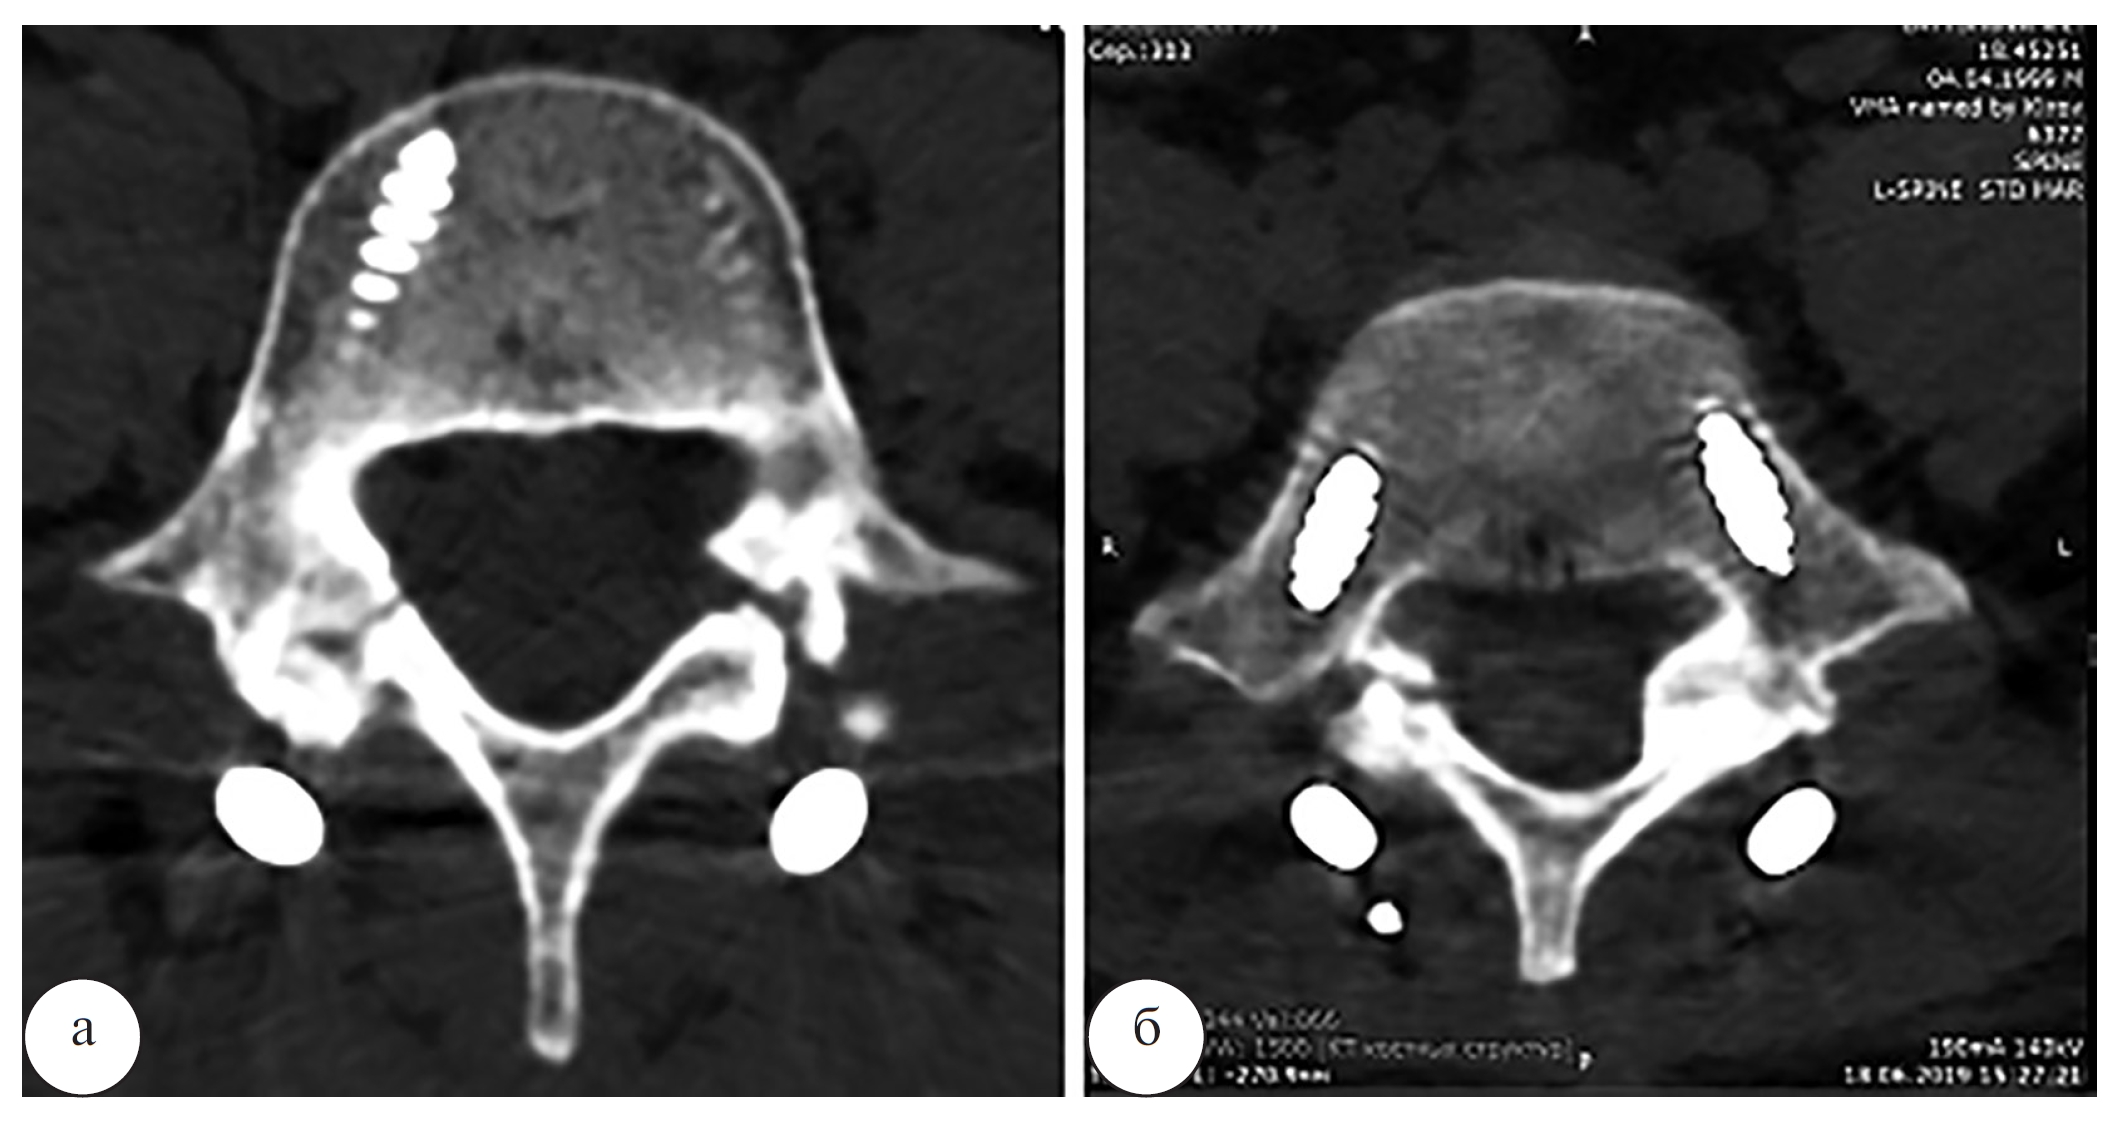

Рис. 6. Компьютерная томограмма L4 и L5 позвонков в аксиальной проекции (а – L4 позвонок, б – L5 позвонок) и МРтомограмма пояснично-крестцового отдела позвоночника в боковой проекции (в) пациента Л. до операции

Наблюдение 2. Пациент Л., 19 лет, рядовой контрактной службы. По данным спондилографии, КТ и МРТ позвоночника (рис. 5, 6) был выявлен двусторонний спондилолиз L4, L5 позвонков, минимальный спондилолистез L4 позвонка (I степени). Выполнена операция: костная аутопластика, задний спондилодез дужек четвертого и пятого поясничных позвонков ламинарно-транспедикулярной системой (рис. 7).